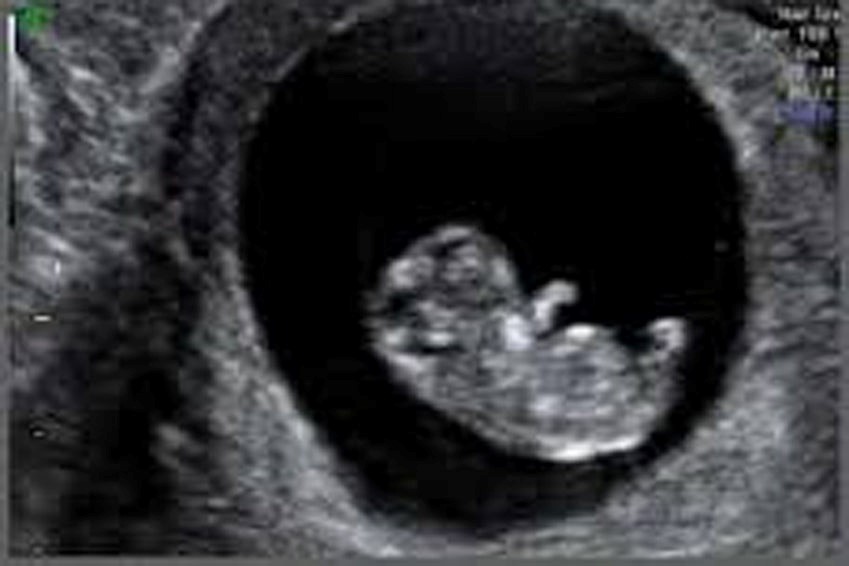

Mediante ecografía transvaginal ya es posible observar el saco gestacional (la bolsa que contiene al embrión y el líquido amniótico).

Ahora el embrión está dentro de una bolsa llena de líquido que crecerá durante todo el embarazo. El embrión tiene forma de tubo, todavía no tiene extremidades. Se empiezan a formar lo que serán huesos, músculos, sistema nervioso. El embrión ya tiene corazón que se contrae en forma rítmica, permitiendo enviar glóbulos rojos con oxígeno a todo su pequeño cuerpo. Por supuesto, en esta etapa el corazón es aún un órgano primitivo, pero ya late y no dejará de hacerlo durante toda su vida. El embrión mide entre 1 y 2 mm.

Mediante ecografía transvaginal ya se puede ver el embrión con latido cardíaco.